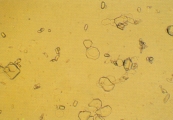

Кальция карбонат может кристаллизоваться в моче лошадей, кроликов, коз, образуя большие желто-коричневые или бесцветные сфероиды с радиальной исчерченностью, или маленькие кристаллы круглой, овальной или гантелеобразной формы (рис. 2 и 3). У собак и кошек эти кристаллы обычно не обнаруживаются. Если в моче обнаруживается гантелеобразный кристалл, то это скорее кальция оксалат моногидрат.

Рис. 3. Сканированная электронная микрофотография некоторых маленьких кристаллов, описанных в рис.2 (увеличение Х 1,800).